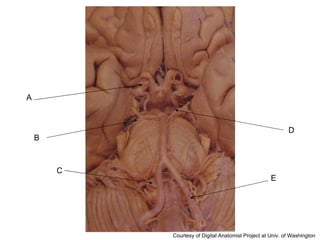

A B C D E Courtesy of Digital Anatomist Project at Univ. of Washington

Answer Key A: anterior communicating artery B: posterior communicating artery C: superior cerebellar artery D: vertebral artery E: anterior cerebral artery